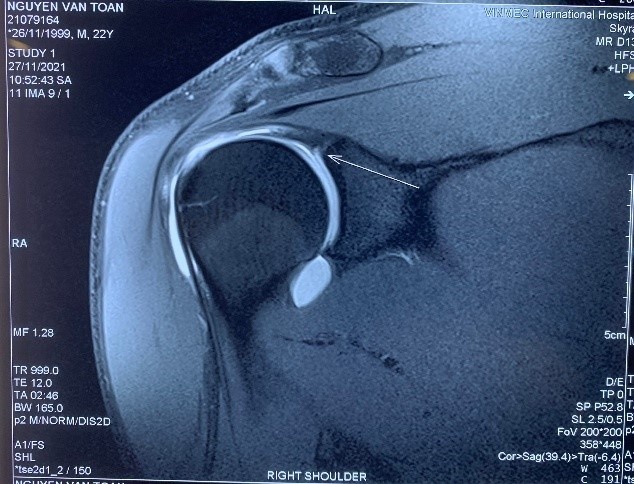

Van Toan chan thuong anh 1

Phim MRI chưa tiêm thuốc cản quang cho hình ảnh tổn thương không thật điển hình.